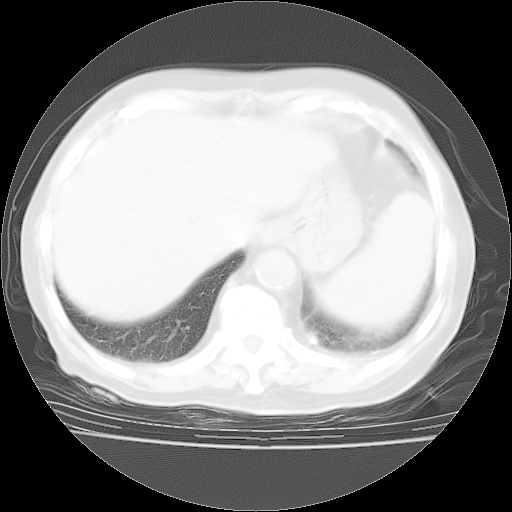

4月28日肺部CT——再次出现类似去年5月9日——透光度降低,“间质性”改变。